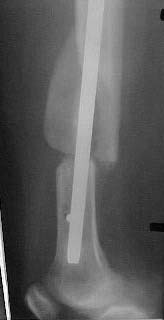

Just have a look at the attached X-rays. The patient had ipsilateral tibial fracture also which was also nailed and locked. The pre operative X.ray was taken in Jan 2001 and the other two x rays were taken in July 2001. These fractures were close nailed.